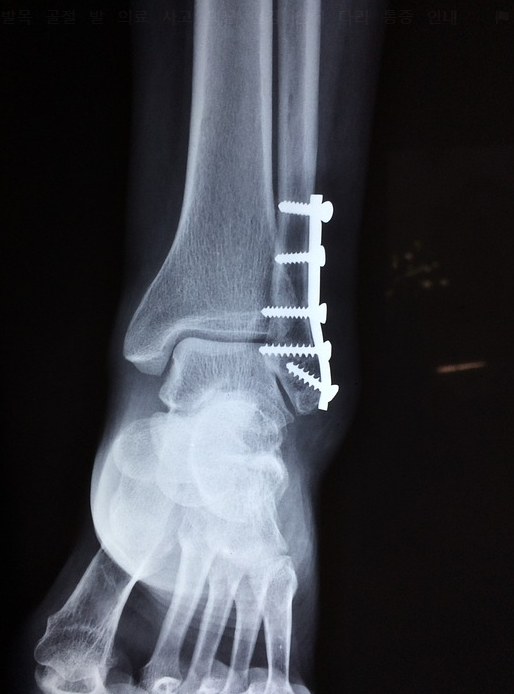

발목 통증 치료법과 원인

발목 통증 치료법